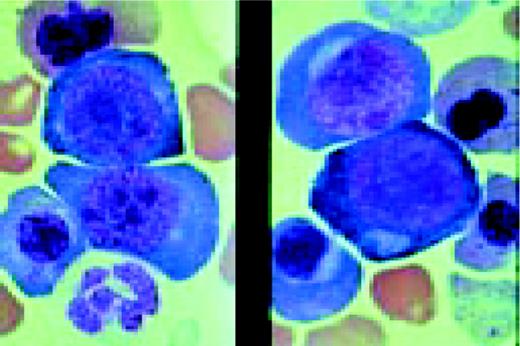

Slide L35

Burkitt's lymphoma. Composite: bone marrow biopsy (L) and bone marrow aspirate (R). Giemsa stained. This 19-year-old male presented with a submandibular tumor in 1997. A biopsy revealed non-Hodgkin's lymphoma, Burkitt's type, according to the REAL classification. Staging revealed stage I disease. He was treated with aggressive polychemotherapy for Burkitt's lymphoma and an allogeneic bone marrow transplant was planned for March 1998. Two weeks before BMT, the patient complained of back pain, and there was a sharp rise of LDH. A bone marrow smear and biopsy revealed massive infiltration by Burkitt lymphoma blasts. Few tumor cells were seen in the blood smear. The slide (R) shows typical Burkitt's lymphoma with vacuolated cytoplasm (ALL-L3 blasts according to the FAB classification). The bone marrow biopsy (L) also shows the typical, leukemia type, interstitial infiltration, leaving the fat cells intact.FIG35